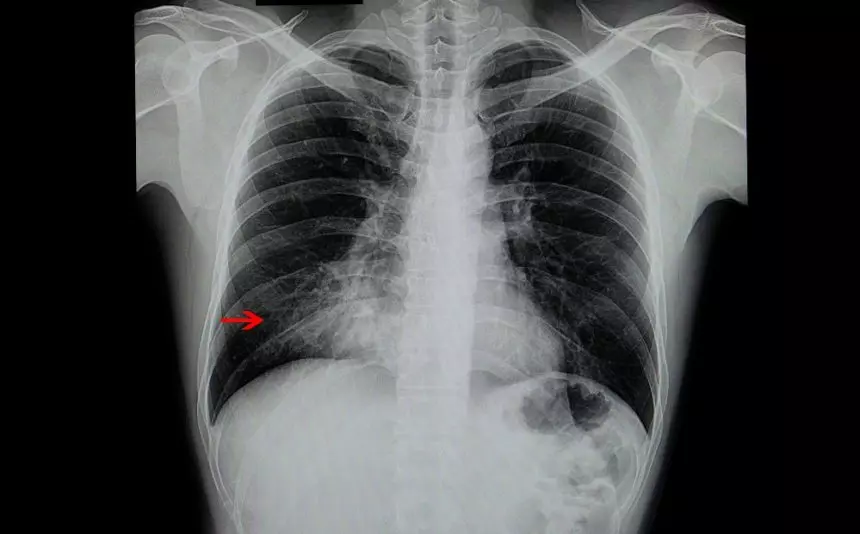

കുഞ്ഞുങ്ങളിലെ ന്യൂമോണിയ

ഇന്ത്യയില് അഞ്ചുവയസ്സില് താഴെയുള്ള കുഞ്ഞുങ്ങളുടെ മരണത്തിനു ഏറ്റവും മുന്നിലായി നില്ക്കുന്ന കാരണം ന്യൂമോണിയാണ്. സാധാരണ ചുമയും ജലദോഷവുമെല്ലാമായി തുടങ്ങുന്ന ന്യുമോണിയയെ സൂക്ഷിക്കണമെന്നതിന്റെ തെളിവാണ് ഈ കണക്കുകകള്.

യുനിസെഫ് കണക്കുകള് പ്രകാരം ഒരു ദിവസം 2,500 കുഞ്ഞുങ്ങള് ന്യൂമോണിയ മൂലം മരിക്കുന്നു. ലോകത്താകെയുള്ള ന്യൂമോണിയ മരണങ്ങളില് 20% ഇന്ത്യയിലാണ്. രോഗപ്രതിരോധ ശക്തികുറഞ്ഞ കുട്ടികളിലാണ് ന്യൂമോണിയ കൂടുതല് അപകടകാരിയായി മാറുന്നത്.

ശ്വാസമെടുക്കാനുള്ള ബുദ്ധിമുട്ടാണ് കുട്ടികളില് കാണുന്ന ന്യൂമോണിയായുടെ പ്രധാന ലക്ഷണം. തുടര്ച്ചയായ ചുമയും ഇടവിട്ടുള്ള പനിയും ന്യൂമോണിയായുടെ മറ്റൊരു ലക്ഷണമാണ്. നിര്ജ്ജലീകരണമാണ് മറ്റൊരു പ്രധാന ലക്ഷം കുട്ടികളുടെ ശരീരത്തില് ജലാംശം പൂര്ണ്ണമായി ഇല്ലാതെയാക്കാന് ന്യൂമോണിയ കാരണമാകുന്നു. രോഗവസ്ഥയിലുള്ള കുട്ടി ചുമയ്ക്കുമ്പോള് ഛര്ദ്ദിക്കുന്നതും ന്യമോണിയായുടെ പ്രധാന ലക്ഷണമാണ്.